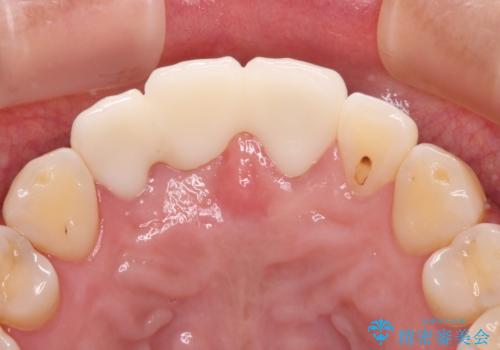

抜歯による歯槽骨や歯肉が陥没して審美障害を起こすことがありますが、今回は仮歯でも違和感のない外観となったため、歯肉移植術を行うことなく仕上げることができました。